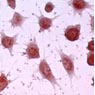

The generated cell line has been growing in culture, in a stable manner for more than 3 years . The cells of the clone, in contrast to the line and primary cells were uniform, survived detachment and could therefore be analyzed by flow cytometry. The KC13-2 clone, like the primary Kupffer cells, constitutively expressed a number of specific functions and structures. These incude: a) the classical macrophage enzymes non-specific esterase (Fig. 1a) and peroxidase; b) two macrophage-specific antigens of unknown function, MOMA-2 (Fig. 1b)

Fig 1a

Fig. 1a: Enzymatic activity (Esterase) of Kupffer cell line